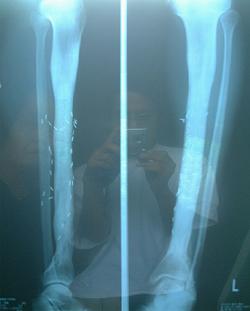

No.03

骨折(三年間で5回骨折を繰り返す)

No.04

上下のボルトを抜く

(一年後)